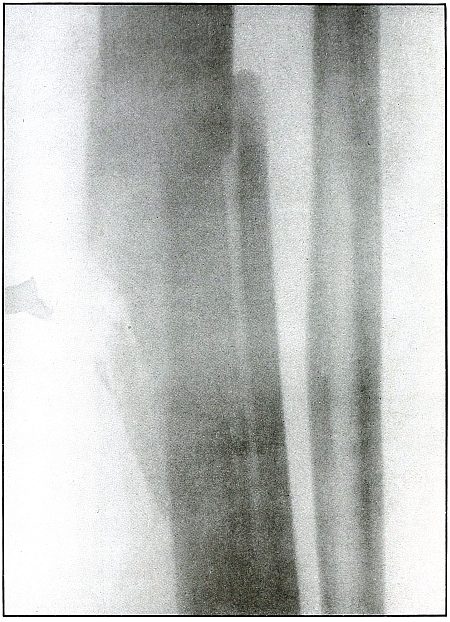

Plate 50.

[Pg 111]

Rifle—Plate 50.

LOWER EXTREMITY.

Gunshot Wound of the Right Thigh,

with Lodgment of the Bullet Behind the Femur.

There is no injury to the bone. The large diameter, shortened length,

and slight density of the shadow show the bullet to be some distance

from and inclining toward the plate and lodged in the muscles behind

the femur, nearer the side away from the photographic plate. It is

difficult to identify the right or left thigh from the radiograph, but

with the history of the wound in the right thigh and the outside of

the leg next to the plate the ball would lie nearer the inside than

the outside of the thigh, nearer the surface behind the femur. As the

shadow shows irregular outline and the location of the bullet low

velocity, the wound was caused by a ricochet shot at very long range.

The treatment is expectant and the course naturally favorable.